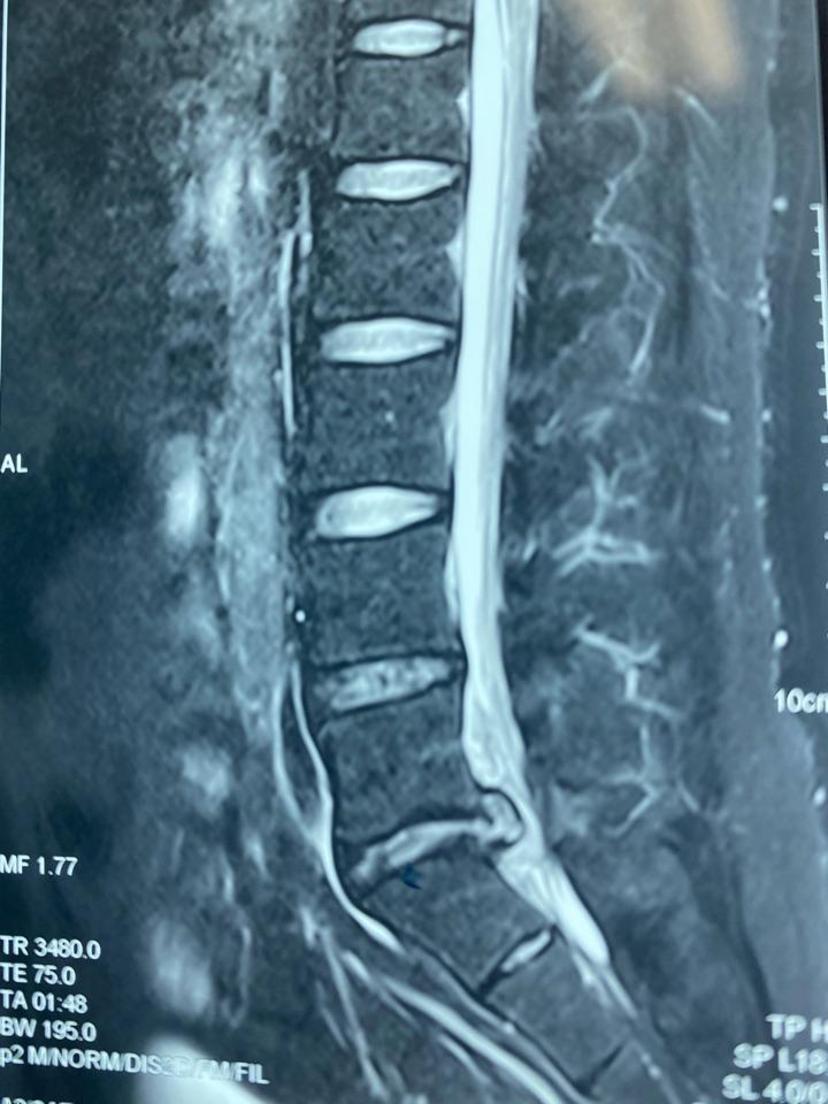

腰5-骶1巨大椎间盘突出、多日卧床行走困难,微创后第二天正常行走,总共住院三晚上!腰5-骶1巨大椎间盘突出右侧神经严重受压取出的压迫物术后右腿痛麻消失,可正常抬腿手术当天切口情况